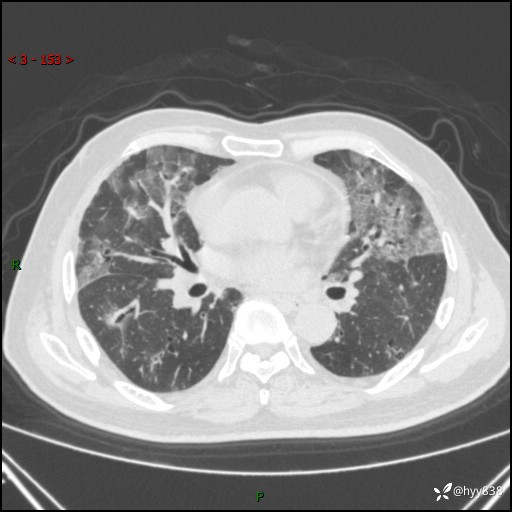

患者性别:男

患者年龄:64岁

简要病史:肝内胆管癌综合治疗后2周余,咳嗽、发热,咳白色泡沫痰。

辅助检查:CT

临床诊断:感染?

讨论:病变性质?